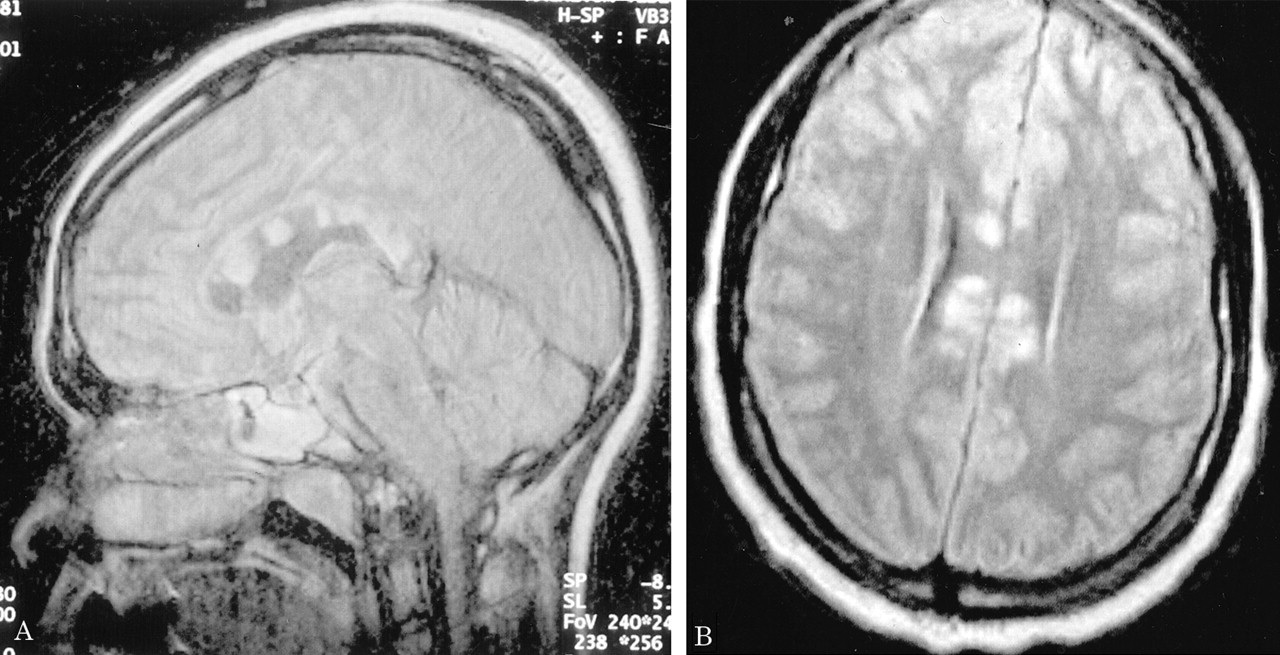

多病灶的幕上的白质病变,包括胼胝体(图1),在所有27个病人,有频繁的参与小脑,中间小脑总花梗,和脑干图1,表)。病变众多,往往是小(3 - 7毫米)但有些小病变成为支流和一些大的(> 7毫米)。19病人实质增强,当明显,导致大脑的粟粒状的外观(图2)。胼胝体的损伤通常是小的,并且涉及中央与周边的相对保留纤维;增强是变量。急性胼胝体的病变(图3)中观察到的活动脑病取而代之的是一个“充满”/穿孔先生出现在后续所有27例(图4),可能代表microinfarctions,没有出现在其他地方。胼胝体,最好在薄片(3毫米厚)矢状T1或T2矢状/质子密度加权图像,由一系列小(3毫米)中央孔相隔7毫米矢状T1和T2矢状/质子密度图像。这些扩展在整个长度的胼胝体。当急性(“雪球”)(见大图3)胼胝体的病变,慢性残余孔较大,尤其是在压部。线性缺陷有时看到的,可能反映microinfarction间接辐射在胼胝体轴突。中央孔(见图4)被认为是由于横向辐射的胼胝体轴突的微型心肌梗塞的可能性。

胼胝体病变的大小通常是3 - 7毫米,暗示闭塞的小前毛细管的小动脉中低于100μm胼胝体。44-46⇓⇓这个小尺寸超出动脉造影术的决议,这是几乎总是在SS患者正常。这些胼胝体的微型心肌梗塞的可能性出现最好在3毫米矢状(T1 / T2 /质子密度/天赋)部分,但更大的矢状“雪球”病变也明显的轴向视图(见图3)。